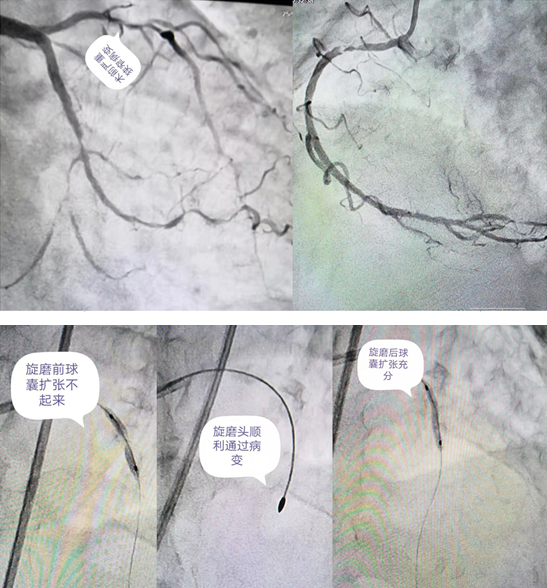

刘大娘今年70岁,家住秀山县。因“上腹疼痛1月余,腹胀纳差6天”到重医附二院秀山分院消化内科住院,伴有糖尿病、高血压病史多年。入院后查心电图及肌钙蛋白异常,经过心内科医生会诊后考虑为急性非ST段抬高型心肌梗死,立即转入心内科治疗,紧急行冠脉造影提示冠脉三支病变:前降支近段至中段弥漫性病变伴严重钙化,狭窄最重达90%;回旋支中远段弥漫性病变,狭窄最重达85%;右冠最重病变狭窄程度达95%。由于病情十分危重,经过规范的冠心病药物治疗,胸痛症状仍没有明显好转;病变处钙化非常严重,于前降支病变处行球囊扩张时,球囊无法扩张。就在刘大娘及家属处于绝望边际之时,在秀山分院挂职副院长的重医附二院心血管内科陈运清教授了解情况后,多次组织心内科医生讨论病情、制定治疗方案,并反复与大娘及家属沟通,最后终于打消顾虑,一致决定择期行血管内超声指导下(IVUS)的冠脉旋磨术和冠脉介入治疗。

没有金刚钻,不揽瓷器活。”7月19日,手术由陈运清教授主刀,首先进行了IVUS检查,提示冠脉病变呈360°钙化;随后,对病变处成功进行了冠脉内旋磨术和支架植入术,并用IVUS复查证实支架覆盖全部病变且贴壁良好,完成血运重建。术后,大娘病情好转,疼痛症状明显消失。26日,阳光普照,当陈教授来到心血管内科A区5号病床时,刘大娘和家人们正在收拾东西准备办理出院。陈教授悬着的心终于落下来了,走到大娘身旁关切地询问病情时,大娘一把握住他的双手,激动地说:陈教授,多亏了您治好了我的病,现在胸口不痛了,胃口好了,吃啥都香了!没想到在这偏远山区,咱老百姓也可以找到大医院的专家来治病!